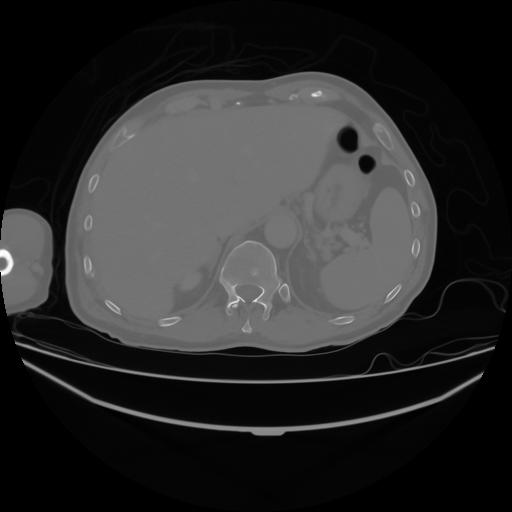

4 CUERPO,CE,Axial,3.0,CUERPO,,